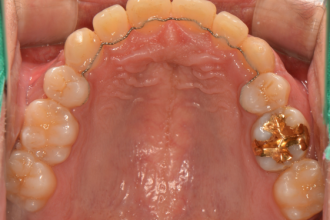

치아교정